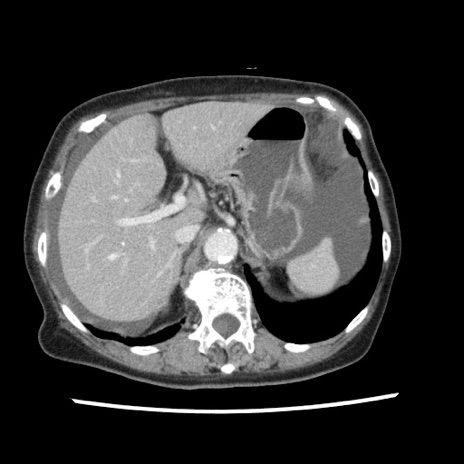

症例1(横断像)

【症例】80歳代女性

【主訴】腹痛

【現病歴】8時間前から腹痛あり来院。

【既往歴】糖尿病、脂質異常症、子宮体癌にて子宮全摘術

【身体所見】意識清明・会話良好だが腹痛で苦悶様、全腹部にわたって反跳痛と圧痛あり

【データ】WBC 13600、CRP 0.14、LDH 224、CK 90